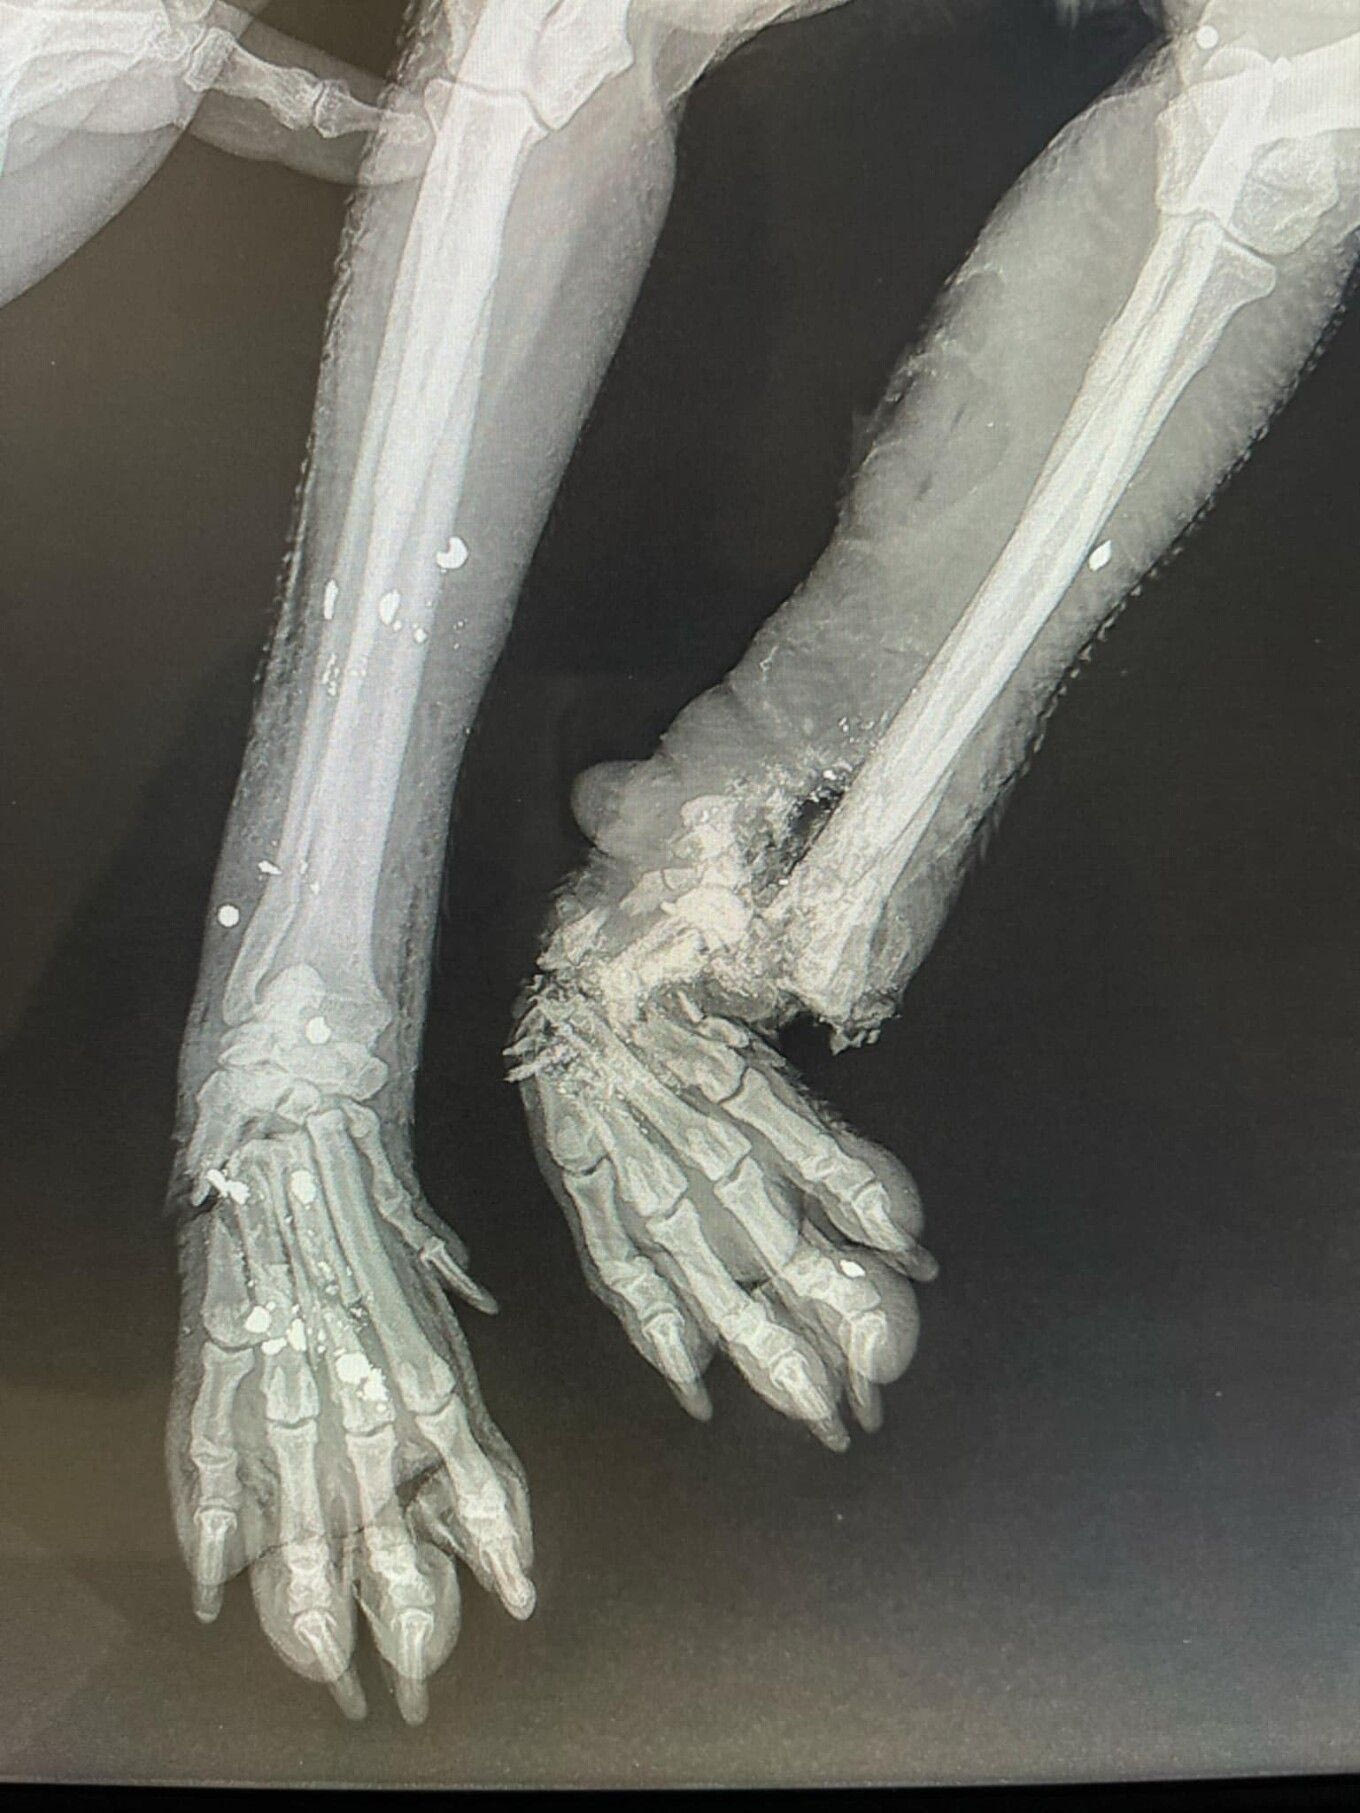

Σύμφωνα με όσα αναφέρει, άγνωστος φέρεται να ξυλοκόπησε και να πυροβόλησε το ζώο, το οποίο εντοπίστηκε σοβαρά τραυματισμένο στην άκρη του δρόμου.

Παρά τις προσπάθειες των κτηνιάτρων, χρειάστηκε ακρωτηριασμός ενός ποδιού.